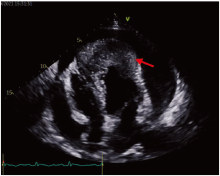

2021-10-09 13∶ 00行超声心动图, 见左右室壁心尖处可见不规则中等偏低回声浸润, 范围约6.5 cm× 3.1 cm, 与原心肌组织分界不清。左右室心尖部异常回声(占位可能); 主动脉瓣轻度返流; 大量心包积液; 室间隔、前壁、侧壁基底段至心尖部应变绝对值降低, 见图3。2021-10-09 14∶ 52行胸部平扫及增强CT显示:左下肺病变伴周围渗出, 大小约6.7 cm× 4.3 cm, 增强不均匀明显强化, 周围局部支气管狭窄闭塞, 考虑肿瘤性病变伴阻塞性肺炎可能并左下肺亚段型不张; 心包积液, 心尖部模糊, 增强见斑片状软组织占位, 考虑转移可能, 见图4。

| 图3 患者超声心动图图像 注:红箭头所示为心尖部占位可能。Fig.3 Echocardiography of the patient Note: The red arrow indicated the possible neoplasm at the apex. |